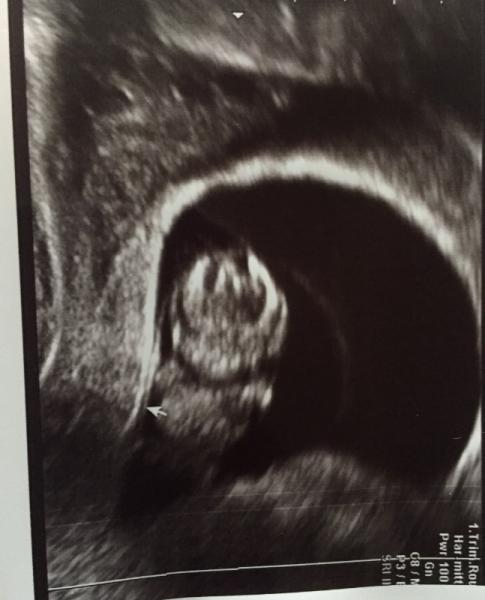

Hallo ihr Lieben, nachdem in den letzten Tagen viel trauriges hier stand, dachte ich wir beginnen den Freitag mal mit was pos. Ich hatte gestern meinen 3. Termin, man konnte die Hände und Füßchen sehen, unser Gummibärchen hat sich bewegt und alles war super. Das Blut war zum Glück auch weg. Ich hab übrigens zur Hilfe Globulis genommen und zwar Bellis Perennis D6. Die sind extra u.a. Gegen Blutung im Uterus. Ich hab 2x 5 Kügelchen pro Tag genommen. Falls jemand noch Hilfe sucht, kann ich das nur empfehlen. Ich bin erleichtert das soweit alles gut ist, in 2 Wochen habe ich den nächsten Termin zur Besprechung wegen Nackenfaltenmessung etc. Ich wünsche euch allen ein schönes we. Ps: das foto ist leider nicht so schön, aber man kann glaub ich sehen das Hände und Füße da sind

Oh nu war das Bild weg, hier das Bild